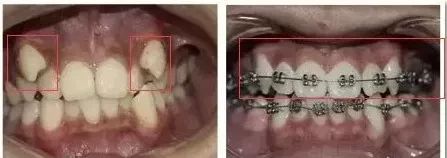

▲

术前X光照

正畸的时间一般在1到2年之间,不过,短短几个月,正畸的效果就可以这么明显!